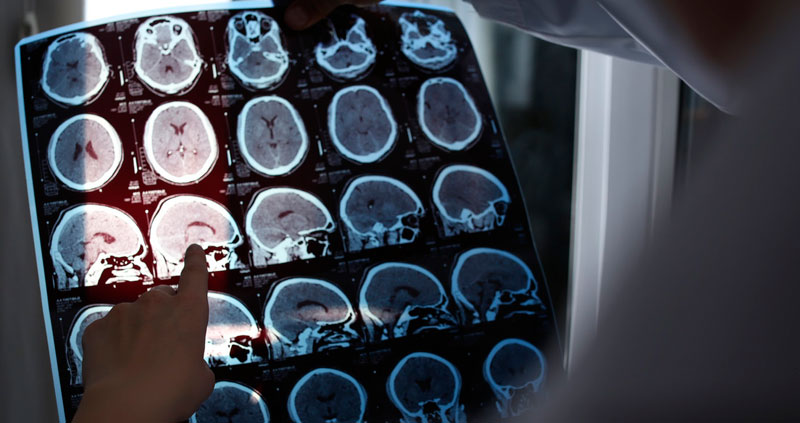

Cuando los médicos examinaron el cerebro del hombre tras su fallecimiento, descubrieron la presencia de proteínas beta-amiloide y tau, que suelen acumularse en el cerebro de las personas con alzhéimer. No obstante, un análisis genético demostró que portaba una rara variante genética denominada RELN-COLBOS, que codifica una proteína llamada reelina.

La reelina evita que se formen estructuras a partir de las hebras enredadas de las proteínas tau, protegiendo una zona especifica del cerebro conocida como corteza entorrinal, que es particularmente sensible al envejecimiento y al alzhéimer. La hermana de este hombre también tenía la mutación PSEN1 y una copia de la variante protectora recién detectada en su cerebro.